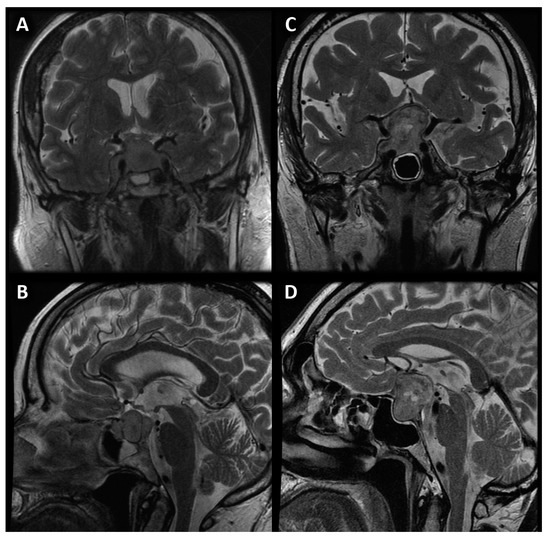

- Mean perfusion parameters for the whole tumor (labeled as rCBV’1)—the arithmetic mean of the perfusion values collected by outlining the tumor with ROIs on each axial slice (Figure 4A).

- Mean of maximum perfusion parameters (labeled as rCBV’2)—the arithmetic mean of the maximum perfusion values collected by outlining the regions with the highest values with circular ROIs (about 30–60 mm2) on each axial slice of the tumor (Figure 4B).

- Maximum perfusion values (labeled as rCBV’3)—the maximum values collected from the whole tumor with a circular ROI (about 30 mm2–60 mm2) (Figure 4B).